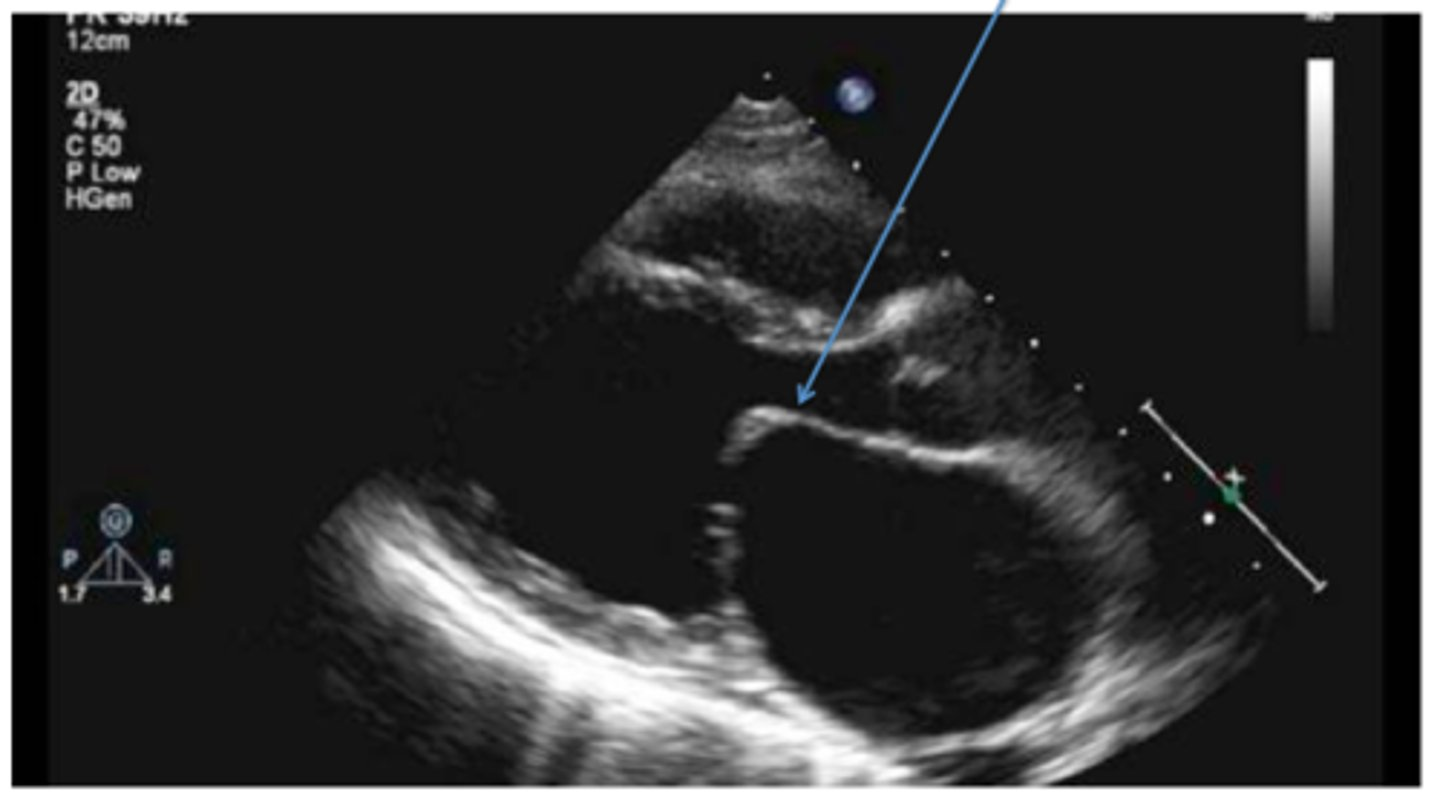

posterior motion of MV leaflets beyond the MV annular plane during systole; hammocking appearance

mitral valve prolapse